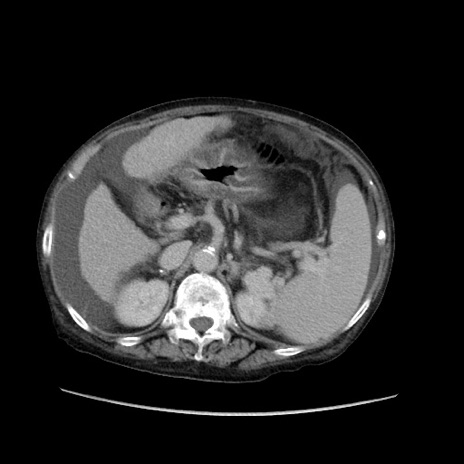

冠状断像